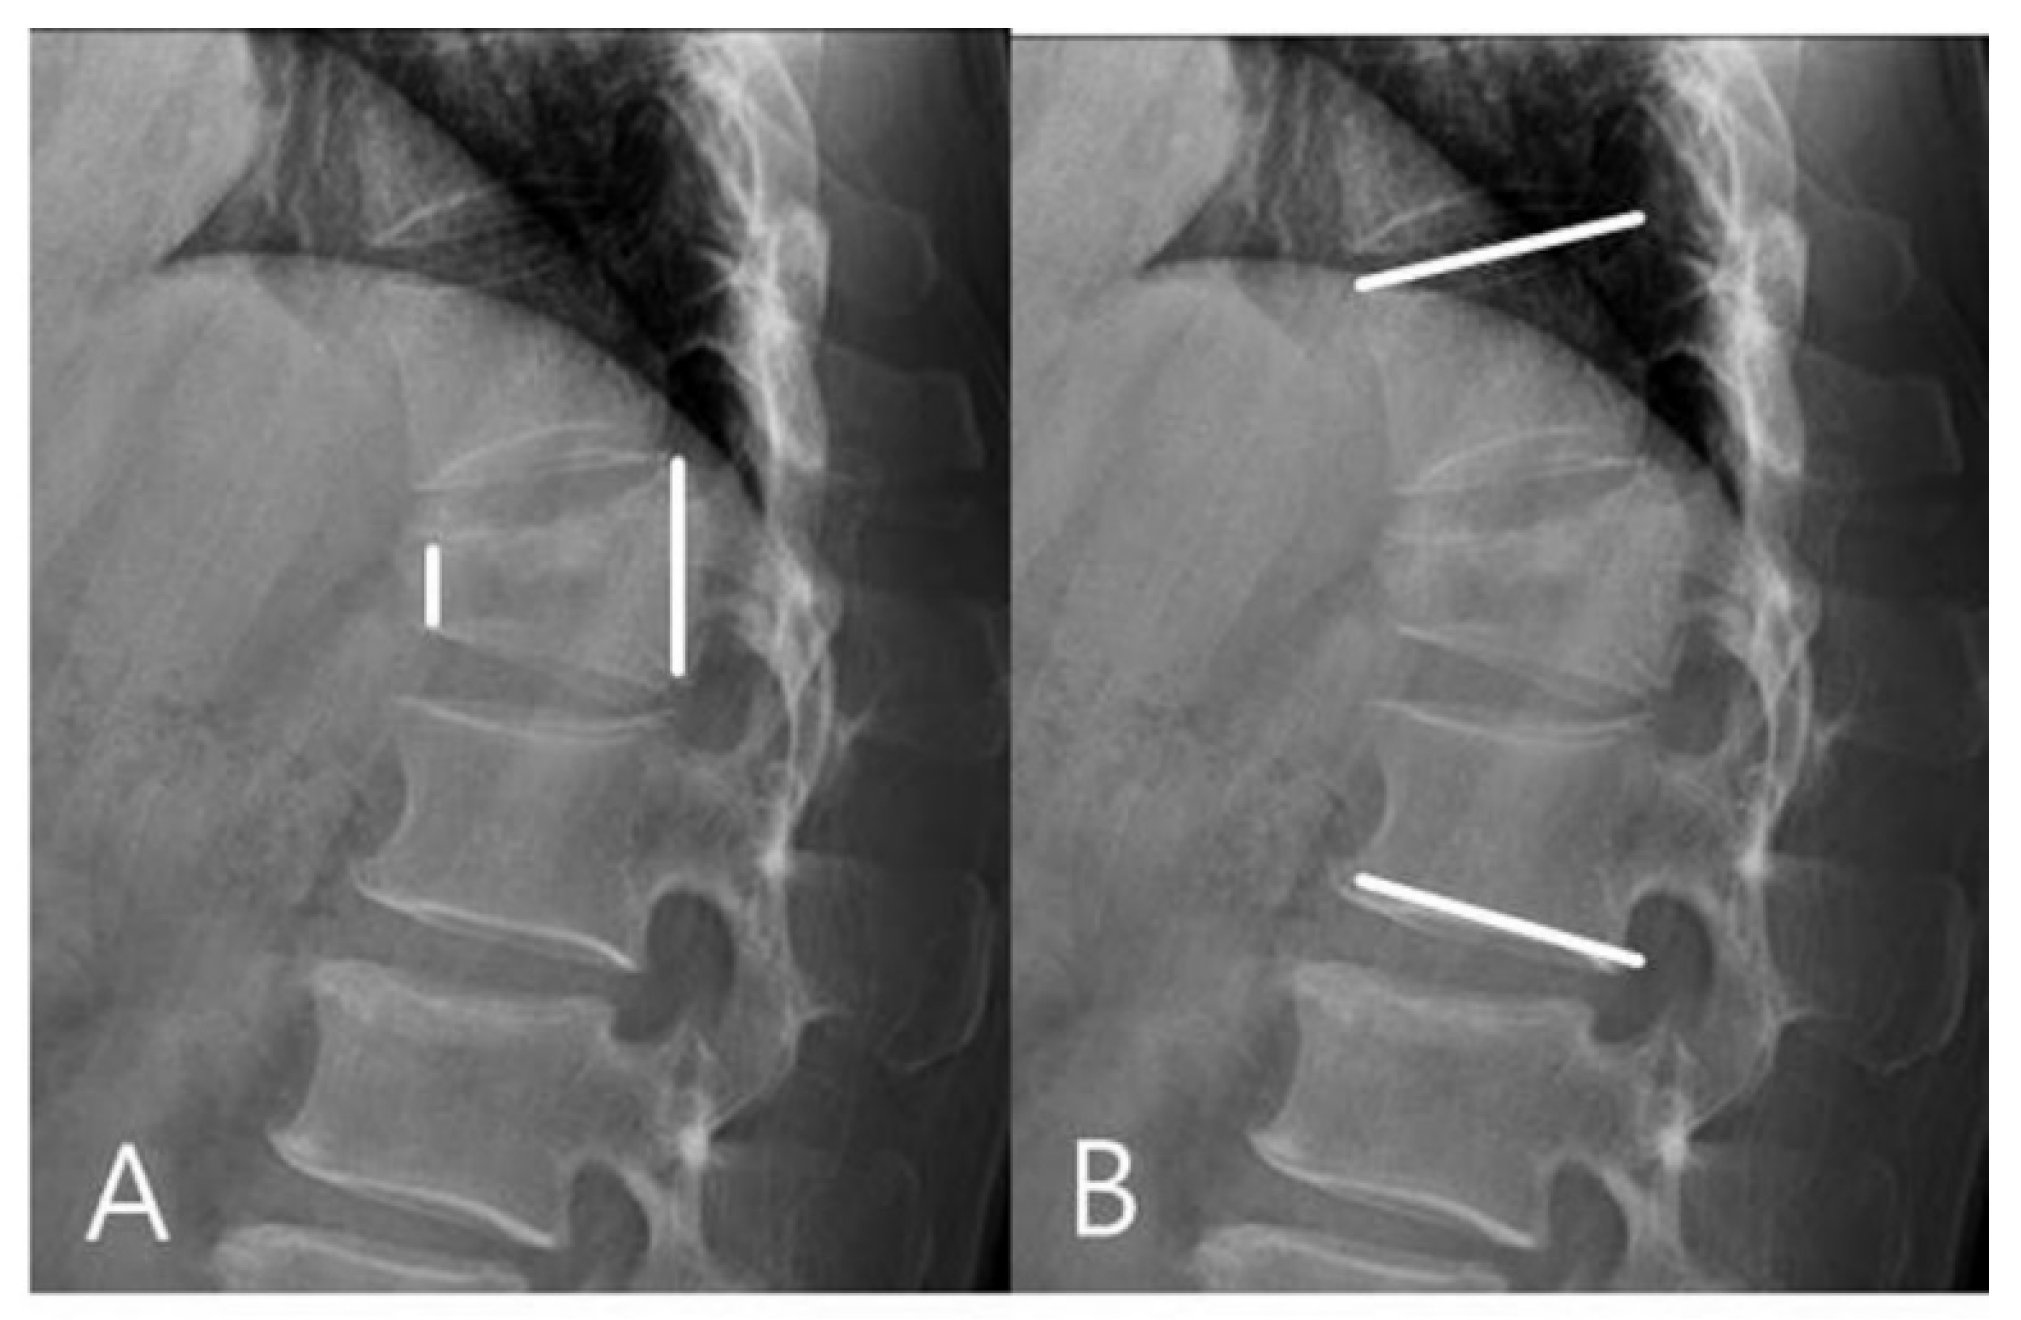

Radiographic evaluations were based on anteroposterior (AP) and lateral views, flexion and extension lateral views, and three-dimensional CT scans. Using the ratio of the heights of the anterior and posterior vertebral wall (on lateral views of the injured vertebral body), we calculated the sagittal index (SI) preoperatively, immediately after surgery, and at the final follow-up (Figure 1). Kyphotic deformity was evaluated on lateral views using the Cobb method. Regional kyphosis angle (RKA) between the superior endplate of the vertebra above the apical (injured) vertebra and the inferior endplate of the apical vertebra below were measured preoperatively, immediately after surgery, and at the final follow-up (Figure 1).

Figure 1.

(A) Sagittal index (SI) was calculated by the ratio of the heights of the anterior and posterior vertebral wall. (B) Regional kyphosis angle (RKA) was measured on lateral radiographs using the Cobb method. RKA between the superior endplate of the vertebra above the fractured vertebra and the inferior endplate of the vertebra below the fractured vertebra were measured.